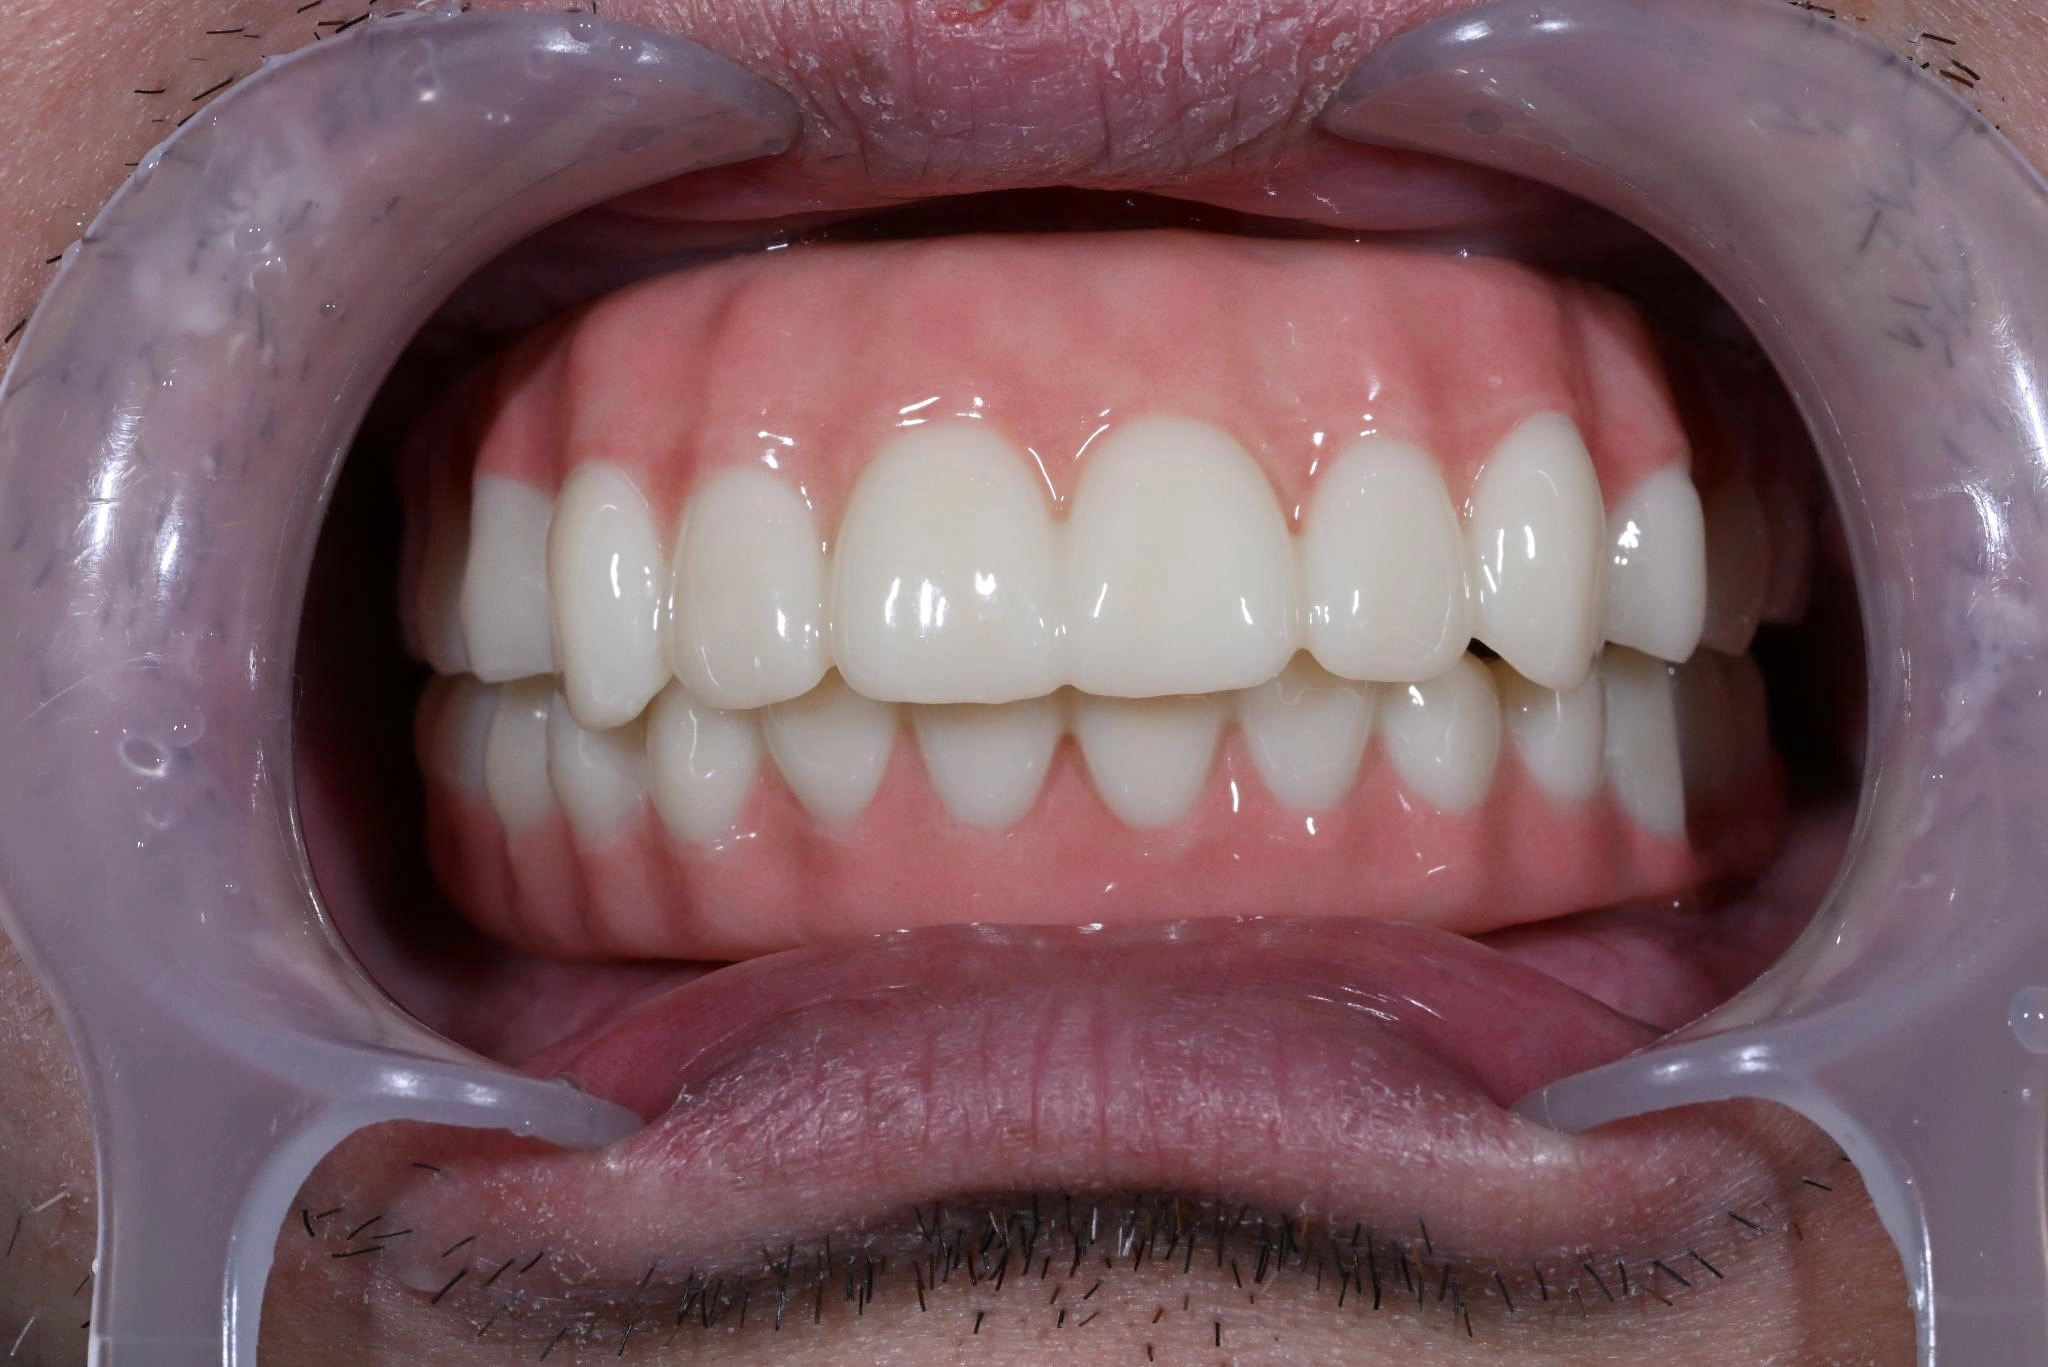

福岡県 46歳(女性)

「根本的な改善をしたい

内容 :上下顎オールオン4ザイゴマ0

費用 :4,822,400円

※モニター価格

期間 :半年

リスク:出血・腫れ・痺れ・痛み

他院で治療を行なっていましたが、根本的な改善には至らないまま不安な状態が続いていました。

カウンセリングで治療の流れや方法について詳しく説明を聞いて手術することを決意しました。

手術前は恐さがあり、緊張していましたが、想像していたような痛みはなく、うたた寝しているような感じでした。気づけば終わっていて、とても満足しています。

元々の自分の歯と比べると仮歯が入った段階でも綺麗になっていて嬉しかったです。この治療法を選んで良かったと思います。